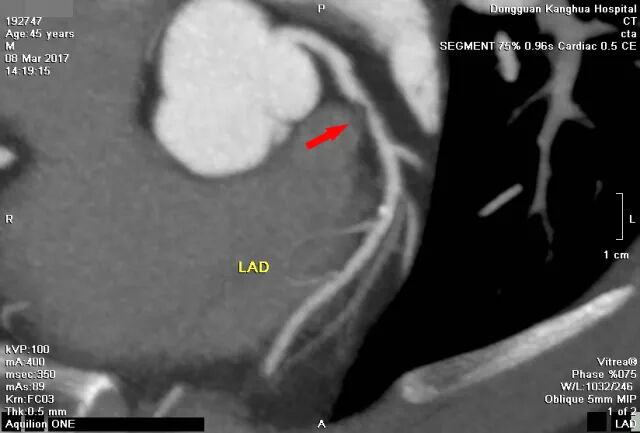

图(1)

冠脉CTA:左前降支近端多发软硬斑块形成,管腔狭窄约80%。